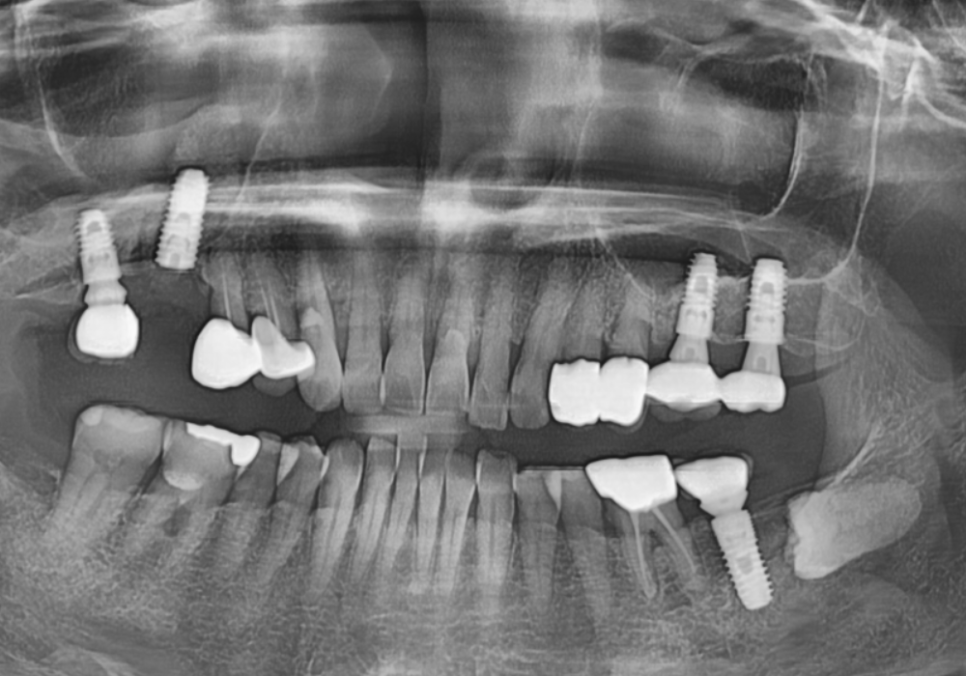

엑스레이를 찍어보니

임플란트 나사를 단단히 잡고 있어야 할

잇몸 뼈가 염증 때문에

까맣게 녹아내려 있었습니다.

231103

흔히 말하는 '임플란트 주위염'이

심각하게 진행된 상태였죠.